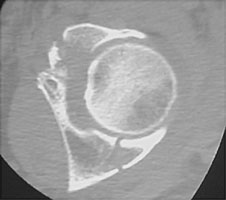

- Click on the image for a larger versionCAxial CT. This image from a different patient shows fractures of both columns of the acetabulum.